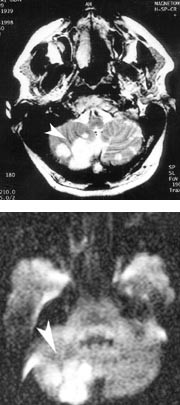

3.6. 1998 fikk han akutt motorisk og sensorisk afasi. Cerebral computertomografi viste hematom temporalt på venstre side (fig 1). Hjerneblødningen ble vurdert å være hypertensivt betinget, og det ble startet med antihypertensiv behandling. 22.8. 1998 fikk han akutt vertigo, kvalme og lett høyresidig ekstremitetsataksi. Over cor hørtes en svak systolisk bilyd. Cerebral magnettomografi viste bilaterale infarkter supra- og infratentorielt, mest uttalt i høyre cerebellum (fig 2), samt rest etter tidligere hematom temporalt på venstre side. EKG viste sinusrytme med venstre ventrikkel-hypertrofi. Pasienten fikk feber og forhøyede infeksjonsparametere (CRP = 170 mg/ml, SR = 70 mm/t og LPK = 21 × 10⁹/l). Antibiotikabehandling ble startet på mistanke om endokarditt. Det var imidlertid ingen oppvekst i flere blodkulturer. Transtorakal og transøsofageal ekkokardiografi viste et stilket myksom utgående fra venstre atrium. Myksomet ble ekstirpert. Mikroskopisk undersøkelse viste myksoid vev, uten tegn til malignitet. Ved senere kontroller ble det ikke påvist residiv av myksom eller flere cerebrale embolier. Pasienten ble 3.2. 1999 innlagt igjen pga. et epileptisk anfall. EEG viste klare cerebrale funksjonsforstyrrelser lokalisert frontotemporalt på venstre side. Han fikk behandling med karbamazepin og har siden vært anfallsfri.

I en studie av 12 pasienter med myksom var hemiparese, afasi, synsforstyrrelse, demens og vertigo første manifestasjon hos fire (8). Vår pasient fikk først afasi, og det ble påvist hematom temporalt på venstre side. Dette har sannsynligvis vært hypertensivt betinget, siden hematomet var manifest i akuttfasen. Det er mindre sannsynlig at det har vært en hemoragisk transformasjon av et iskemisk infarkt betinget i emboli fra myksom i venstre atrium. Senere fikk pasienten vertigo og ataksi, og det ble påvist multiple infarkter av ny og eldre dato.

Sentralnervøse infarkter er vanlige nevrologiske manifestasjoner ved myksom, og ble påvist hos seks av 13 pasienter med venstre atrie-myksom (6). Sykehistorie med gjentatte nevrologiske lesjoner i forskjellige deler av sentralnervesystemet er derfor typisk ved embolier fra myksom (9).